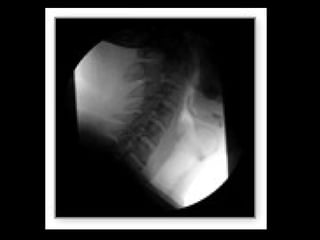

Digital  spot film images and photospot images may be acquired by using the same  digital   fluoroscopy  system.  Individual frames from a  digital   fluoroscopy  sequence can be stored  digital ly and can be used instead of conventional spot film and photospot images.  Digital  photospot images will have the same characteristics (eg, resolution) as  digital  fluoroscopic images.

Digital spotfilm images and photospot images may be acquired by using the same digital fluoroscopy system. Individual frames from a digital fluoroscopy sequence can be stored digital ly and can be used instead of conventional spot film and photospot images. Digital photospot images will have the same characteristics (eg, resolution) as digital fluoroscopic images.